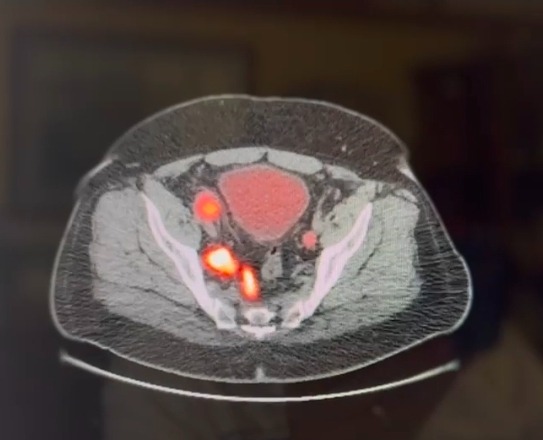

Ray Cobb is a devoted husband, father, and self-employed business owner who has always worked hard to provide for his family. In October 2025, Ray received the life-changing diagnosis of stage 4 metastatic prostate cancer. Since then, his health has declined, making it impossible for him to keep up with the demands of his business. This has led to a significant drop in income, just as his medical expenses have soared.

Ray’s treatment plan is intensive and ongoing. He currently takes three daily medications, receives hormonal treatment every six months, and will begin radiation treatments at the end of February. Each week, Ray must travel two hours each way to his treatment center, three times a week. These trips, along with the costs of tests, lab work, and new insurance premiums at the start of the year, have created a heavy financial burden for Ray and his family.

In the first 2 and half months after his diagnosis the bills for doctor visits, consultations, and beginning treatment totalled nearly $7000. Some of the labwork has been done to test for genetic markers which came back with results showing high percentages for inheritated gene mutations.